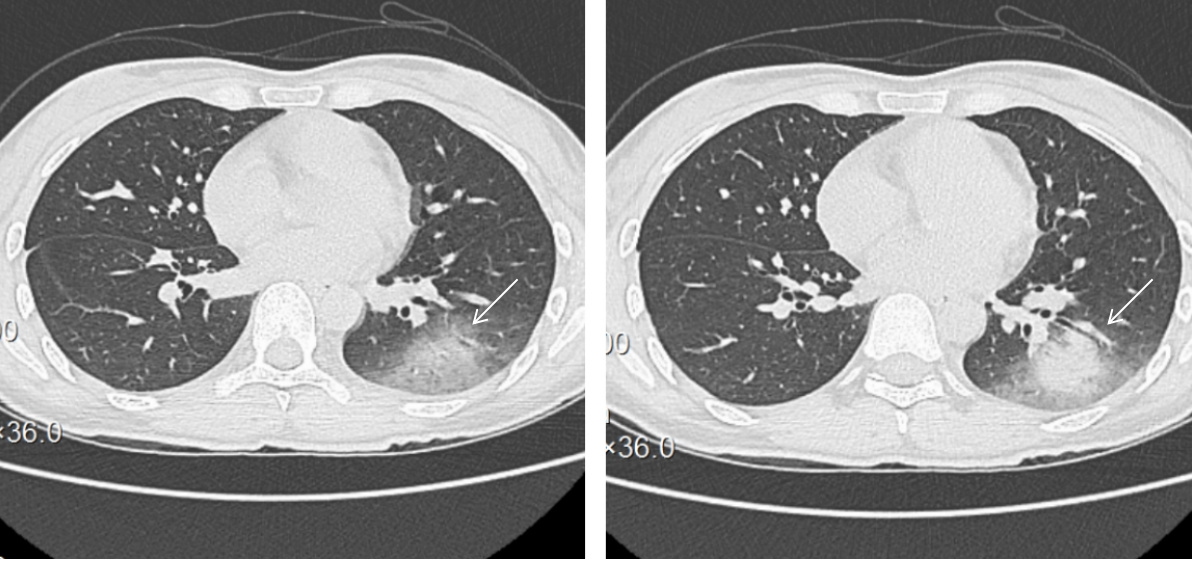

1 资料与方法 1.1 入院病历资料患者女性,36岁,因“反复发热7 d”于2025年6月25日入住本院感染科。入院7 d前出现发热,最高体温39℃,伴畏冷、寒战,6月24日就诊当地医院,查血常规未见明显异常,C反应蛋白26.2 mg/L,红细胞沉降率50 mm/h,纤维蛋白原5.69 g/L,血清生化,丙氨酸氨基转移酶331.9 U/L,天冬氨酸氨基转移酶246.6 U/L,谷氨酰转移酶120.7 U/L, 碱性磷酸酶109.1 U/L,胸部CT:左下肺异常密度影,炎症性病变可能”, 予保肝、“左氧氟沙星0.5 g静滴, 1次/d、头孢曲松2 g静滴, 1次/d”抗感染治疗,但仍反复发热,转诊本院,复查胸部CT:左肺下叶炎症改变,考虑感染性病变(图 1)。既往体健,否认任何毒物、药物上瘾史。入院查体:体温37℃,脉搏77次/min,呼吸20次/min,血压97/55 mmHg。神志清楚,精神疲乏,双肺呼吸音稍粗,双肺未闻及干湿性啰音。神经系统查体未见异常。入院诊断:社区获得性肺炎; 肝功能不全。

| 图 1 胸部CT提示: 左肺下叶见斑片状高密度影,部分呈磨玻璃样改变,可见支气管充气征,边缘模糊,密度不均(箭头所示) |